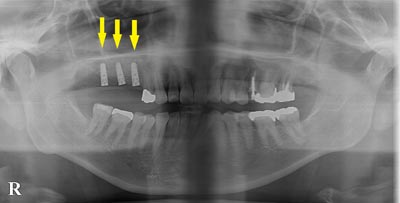

写真は初診時の患者様のレントゲン写真です。左右とも、上顎第一大臼歯を失っていました。通常のレントゲン写真では、骨量が十分かと思われましたが、CTを撮影してみると、黄色の矢印部位、左側では、少し骨の高さが足りませんでした。

写真は初診時の患者様のレントゲン写真です。左右とも、上顎第一大臼歯を失っていました。通常のレントゲン写真では、骨量が十分かと思われましたが、CTを撮影してみると、黄色の矢印部位、左側では、少し骨の高さが足りませんでした。

CTを撮影して、測定すると、右側はギリギリ10mmぐらいの高さで、左側は6mmほどしかありませんでした。

CTを撮影して、測定すると、右側はギリギリ10mmぐらいの高さで、左側は6mmほどしかありませんでした。

そこで、左側はソケットリフトを併用して行いました。インプラント埋入手術後のCT、黄色の矢印部分、インプラント周囲にドーム状に補填材が白く写り、インプラントがしっかりと埋入できています。

そこで、左側はソケットリフトを併用して行いました。インプラント埋入手術後のCT、黄色の矢印部分、インプラント周囲にドーム状に補填材が白く写り、インプラントがしっかりと埋入できています。